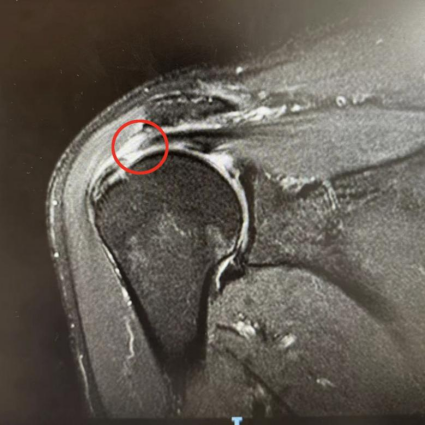

在郭老伯的比划和亲属的手语翻译下,运动医学科副主任韦钊岚慢慢了解了患者的病情,初步判定为肩袖损伤。此后的磁共振检查也验证了她的判断,老人的肩袖损伤已达到十分严重的程度。

肩袖是由冈上肌、冈下肌、肩胛下肌、小圆肌肌腱分布在肩关节前、后、上方包绕肩关节形成的袖套样的组织。每一根肌腱都在肩关节内收、外展、前屈、后伸、上举、环转中起到重要作用,任何一根肌腱损伤,其所对应的功能则明显减弱,肌腱损伤就造成了肩袖损伤。

对于肩袖损伤,韦钊岚医生建议尽早治疗。轻微的肩袖损伤,通过正规的保守治疗能获得较好疗效,保守治疗无效的,应尽早行手术治疗。针对郭老伯的情况,运动医学科团队在关节镜下对撕裂的冈上肌腱进行复位缝合固定,手术非常成功。